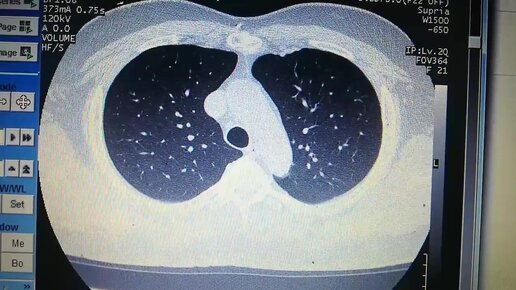

Компьютерная томография. Краткий обзор.